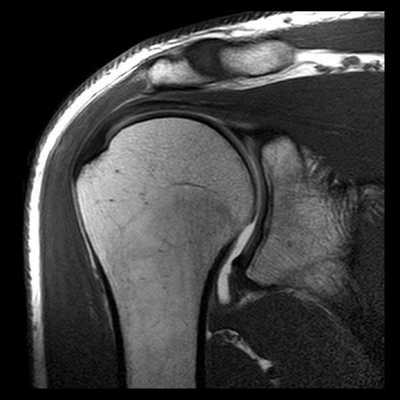

МРТ или КТ плечевого сустава

МРТ и КТ плечевого сустава являются двумя основными высокоинформативными способами диагностировать патологии в области плеча. У многих пациентов возникает вопрос, в чем же отличия между МРТ и КТ (МСКТ) плеча, и что лучше: сделать МРТ плечевого сустава или КТ. Давайте разбираться вместе.

У каждого способа обследования имеются свои преимущества и недостатки. На сегодняшний день ведущую роль в визуализации вне- и внутрисуставных структур плечевого сустава играет МРТ, которая позволяет выявлять мягкотканные и костные повреждения в суставах. Она может осуществляться по двум базовым протоколам - бесконтрастная томография и МРТ плечевого сустава с применением парамагнитных контрастных веществ (она же МР артрография). Лидирующую роль в оценке состояния костей плеча играет спиральная компьютерная томография.

Когда МРТ плечевого сустава лучше, чем КТ плеча

В медицинских центрах СПб обследование плечевого сустава с помощью магнитного резонанса является профилирующим диагностическим исследованием патологий суставных тканей. Именно МРТ плечевого сустава дает возможность получить данные о состоянии суставов, мягких тканей и хрящей. Томография плеча хорошо покажет:

- причины непонятной боли в плече, хруста в плече;

- последствия травмы в области плечевого сустава, перелома;

- место разрыва связок, периодических вывихов;

- причины припухлости в области плеча;

- ущемление нервов, сухожилий.

МРТ также позволяет отличить здоровые ткани от поврежденных при предположении на опухоль или раковые метастазы, помогает оценить картину травм и их месторасположение.